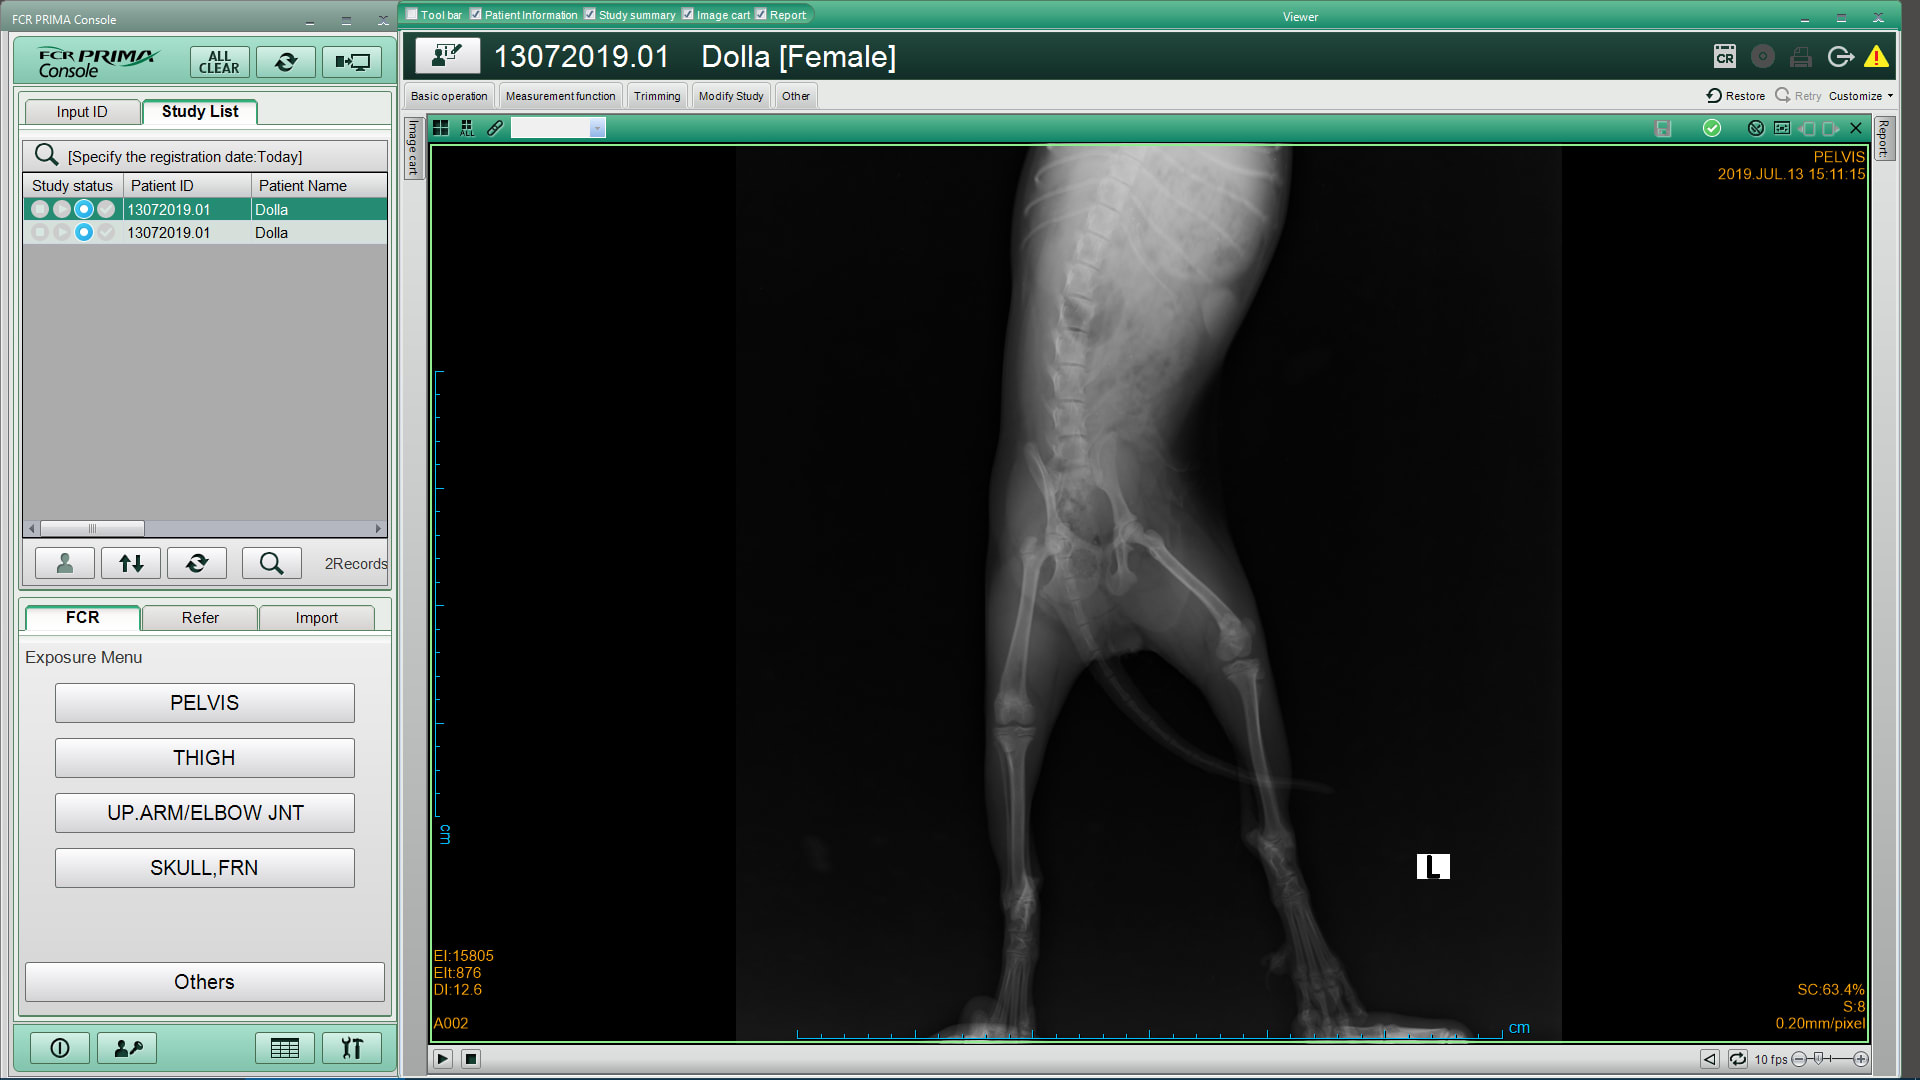

Hi, Someone please help me, this is the image I got from the vet, they said my dog snapped the femur-the truth hurts, it just six months earlier, cancers are still running normal jump , You helped me see there is any method that can treat for my dog, I'm very sad. Looking forward to hear from you. Thank you so much :(

Thanks for using Petco Pet Education Center, formerly Petcoach! Yes, Dolla has a broken femur. The best treatment is a surgical repair. I recommend discussing the surgery with your vet. After surgery she will need 6-8 weeks to heal. Luckily she is young so she should do well with the procedure and recovery. Good luck and kisses to Dolla!